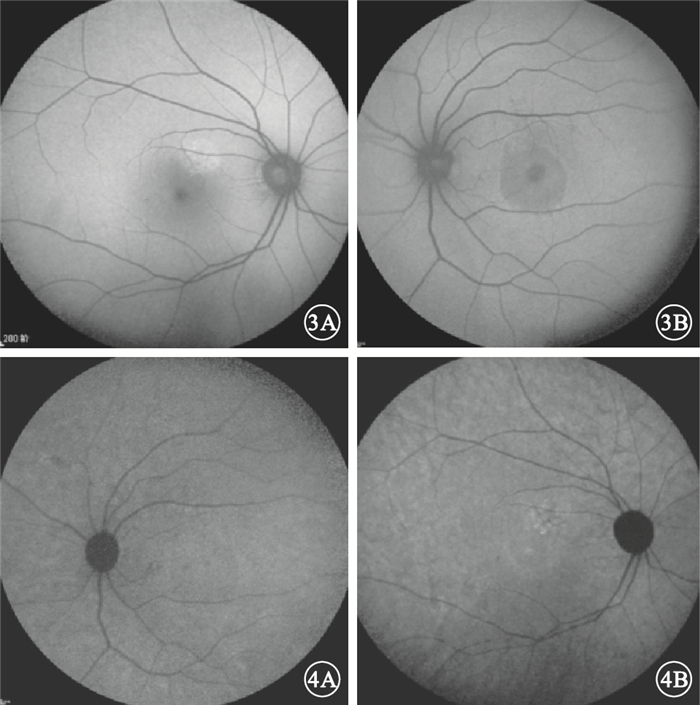

急性CSC 47只眼中,與FFA檢查可見的滲漏點對應處BLAF可表現為點狀或片狀強熒光(圖 3A)、點片狀弱熒光或斑駁熒光(圖 3B)以及無異常改變等多種表現形式。可觀察到神經上皮層脫離35只眼,占74.5%。其中,表現為圓形或橢圓形弱熒光21只眼,占60.0%,表現為強熒光14只眼,占40.0%。IRAF表現以點狀、片狀弱熒光或斑駁熒光(圖 4A)為主,強熒光(圖 4B)及無異常改變者比例相當。可觀察到神經上皮層脫離26只眼,占55.3%;均表現為圓形或橢圓形弱熒光(表 1)。

圖3

急性CSC患眼BLAF像。3A.圖 1A同眼,與FFA檢查可見的滲漏點對應處表現為片狀強熒光;3B.圖 1B同眼,與FFA檢查可見的滲漏點對應處表現為斑駁熒光??圖 4?急性CSC患眼IRAF像。圖 4A.圖 1B同眼,與FFA檢查可見的滲漏點對應處表現為點狀弱熒光;4B.圖 1A同眼,與FFA檢查可見的滲漏點對應處表現為點狀強熒光

圖3

急性CSC患眼BLAF像。3A.圖 1A同眼,與FFA檢查可見的滲漏點對應處表現為片狀強熒光;3B.圖 1B同眼,與FFA檢查可見的滲漏點對應處表現為斑駁熒光??圖 4?急性CSC患眼IRAF像。圖 4A.圖 1B同眼,與FFA檢查可見的滲漏點對應處表現為點狀弱熒光;4B.圖 1A同眼,與FFA檢查可見的滲漏點對應處表現為點狀強熒光

急性CSC 47只眼中,與FFA檢查可見的滲漏點對應處BLAF可表現為點狀或片狀強熒光(圖 3A)、點片狀弱熒光或斑駁熒光(圖 3B)以及無異常改變等多種表現形式。可觀察到神經上皮層脫離35只眼,占74.5%。其中,表現為圓形或橢圓形弱熒光21只眼,占60.0%,表現為強熒光14只眼,占40.0%。IRAF表現以點狀、片狀弱熒光或斑駁熒光(圖 4A)為主,強熒光(圖 4B)及無異常改變者比例相當。可觀察到神經上皮層脫離26只眼,占55.3%;均表現為圓形或橢圓形弱熒光(表 1)。

圖3

急性CSC患眼BLAF像。3A.圖 1A同眼,與FFA檢查可見的滲漏點對應處表現為片狀強熒光;3B.圖 1B同眼,與FFA檢查可見的滲漏點對應處表現為斑駁熒光??圖 4?急性CSC患眼IRAF像。圖 4A.圖 1B同眼,與FFA檢查可見的滲漏點對應處表現為點狀弱熒光;4B.圖 1A同眼,與FFA檢查可見的滲漏點對應處表現為點狀強熒光

圖3

急性CSC患眼BLAF像。3A.圖 1A同眼,與FFA檢查可見的滲漏點對應處表現為片狀強熒光;3B.圖 1B同眼,與FFA檢查可見的滲漏點對應處表現為斑駁熒光??圖 4?急性CSC患眼IRAF像。圖 4A.圖 1B同眼,與FFA檢查可見的滲漏點對應處表現為點狀弱熒光;4B.圖 1A同眼,與FFA檢查可見的滲漏點對應處表現為點狀強熒光